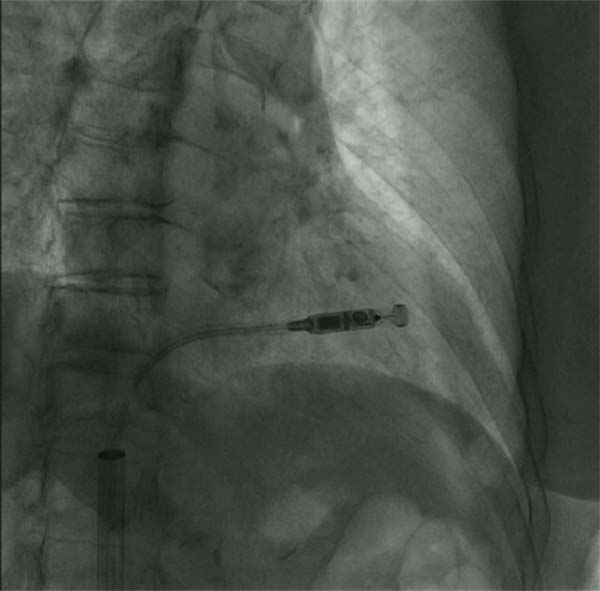

11月15日,心血管内科在导管室为患者实施无导线起搏器治疗,手术取得圆满成功,手术过程顺利,患者术后窦性心律平稳,起搏器起搏感知功能良好。心血管内科凭借精湛的医术和丰富的临床经验,成功挽救了高龄老人的生命,为进一步接受其他治疗打下了良好的基础。

据了解,无导线起搏器俗称胶囊起搏器,就像一粒胶囊药物大小,体积较传统起搏器减少93%,是世界上最小的起搏器,目前我们使用的型号重量只有1.7g,寿命可达13-15年。主要特点是体积小,抗核磁,可以接受1.5T和3.0T全身核磁检查,同时植入方便快捷,经股静脉途径就能完成,术后恢复更快,两天就可恢复日常工作和生活。此例无导线起博器手术的成功实施,标志着应急总医院心血管内科的救治技术迈上了新台阶、实现了新跨越。

起搏器释放前